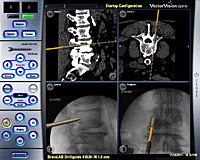

La fijación vertebral consiste en la colocación o implante de tornillos para fijar las vertebras ya sea a nivel cervical, dorsal o lumbar. La utilización de la navegación en este tipo de cirugía, que viene a ser como un GPS, permite realizar dichos implantes con un porcentaje de éxito del 97,6% evitando lesiones del nervio y re-intervenciones por mala posición de los tornillos como puede ocurrir con las técnicas clásicas. Para realizar esta cirugía utilizamos un ordenador y unas cámaras ópticas que permiten, mediante la introducción de las imágenes de una TC preoperatoria y las de unas radiografías realizadas en la posición real quirúrgica del paciente, realizar una fusión de las mismas convirtiéndolas en imágenes 3D reales-virtuales. A través de un instrumental especial, podemos visualizar en directo la trayectoria de los tornillos.